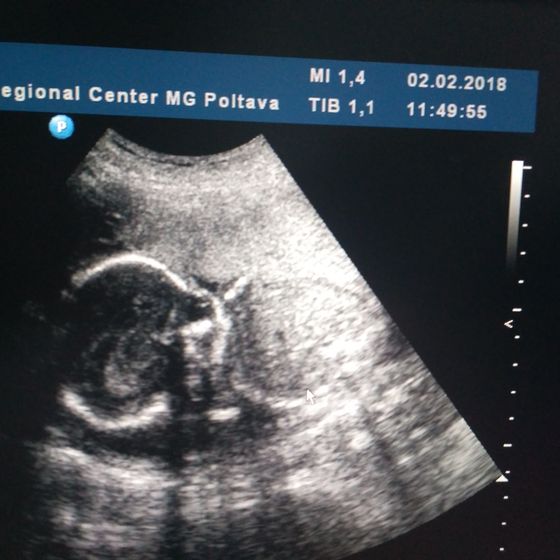

Вобщем попали мы сегодня на узи. С мальчиком моим все хорошо ? растём срок в срок. Как всегда пытался отвернуться) Наша супер узистка конечно закатывала глаза когда я просила мужа позвать и когда он попросил сфоткать экран. Я думала у нее глаза за лоб уйдут??. Ну сегодня она даже немного в настроении была?вопрос только вот в чем… ей не понравилась моя плацента… степень зрелости 1, сказала, что рыхлая… что это значит? Сказала, что типо какой иммунитет такая и плацента… а так все хорошо.

Растите дальше большими и здоровыми? А у меня даже на экран полностью не поместился) сделали отдельно фото ручек, ножек и личика в 3д) я поэтому платно пошла, чтобы все нормально показали, в жк вообще не хотелось(

Спасибо) это у генетиков. У них там экран большой. Поэтому там помещаемся) а в жк тоже не)) а какой вес у вас был на 2 скрининге?